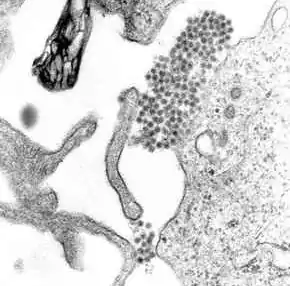

Once inside the skin, dengue virus binds to Langerhans cells (a population of dendritic cells in the skin that identifies pathogens).[46] The virus enters the cells through binding between viral proteins and membrane proteins on the Langerhans cell, specifically, the C-type lectins called DC-SIGN, mannose receptor and CLEC5A.[30] DC-SIGN, a non-specific receptor for foreign material on dendritic cells, seems to be the main point of entry.[33] The dendritic cell moves to the nearest lymph node. Meanwhile, the virus genome is translated in membrane-bound vesicles on the cell's endoplasmic reticulum, where the cell's protein synthesis apparatus produces new viral proteins that replicate the viral RNA and begin to form viral particles. Immature virus particles are transported to the Golgi apparatus, the part of the cell where some of the proteins receive necessary sugar chains (glycoproteins). The now mature new viruses are released by exocytosis. They are then able to enter other white blood cells, such as monocytes and macrophages.[30]